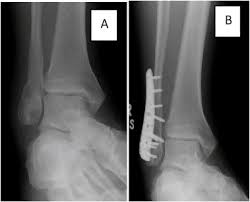

For some reason, no one seems to like lateral knees, especially students. Lateral malleolar fracture with deltoid injury or bimalleolar or trimalleolar fracture. 687 x 522 png 292 кб. The other two are the lateral and the posterior malleolus. Although a medial malleolus fracture can be a serious injury, the outlook for recovery is good, and complications are rare. The medial malleolus is the largest of the three bone segments that form your ankle. The lateral malleolus provides key stability against excessive eversion of the ankle and foot. Radiograph showing lateral malleolus fracture.

Radiograph showing lateral malleolus fracture. Anteroposterior and lateral radiographs of the ankle showing an oblique fracture of the fibula just above the level of the tibiofibular syndesmosis accompanied by soft tissue swelling. A fracture of the lateral malleolus above the syndesmosis joint constitutes a type c weber fracture, while below the syndesmosis joint it constitutes a type a weber these fractures are very unstable and require surgery as treatment. Causes, symptoms, and diagnosis of bimalleolar fractures. Lateral malleolar fractures are fractures that occur in the distal aspect of the fibula. Here's what you need to know. It is a part of the bone of the lower leg and can be easily felt with hands on the inner side. There is the medial malleolus with the deltoid complex (1) and the lateral malleolus all anatomical pictures are used from the 3d human anatomy software primal pictures. This information will guide you through the next 6 weeks of your rehabilitation. Fractures of the human ankles. However, only one case was worse than. 687 x 522 png 292 кб. A lateral malleolus fracture is a fracture of the fibula.

Radiograph showing lateral malleolus fracture malleolus fracture. Malleolar fractures include injuries of bones (malleoli) and or ligaments.